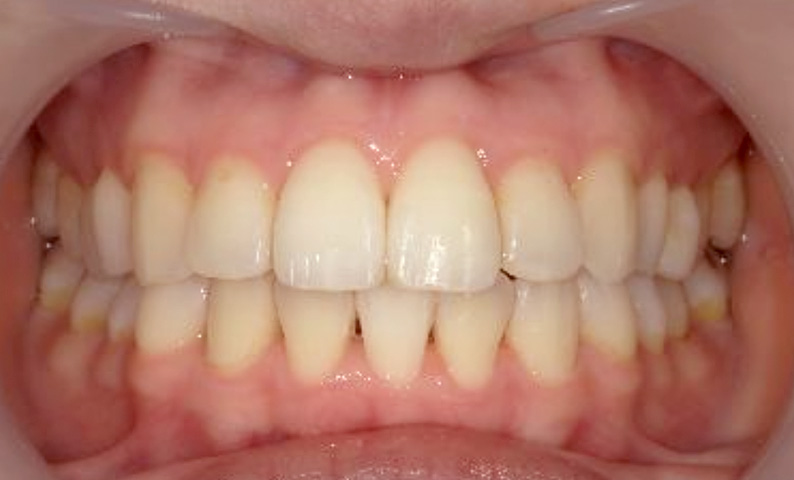

症例_024 上顎だけの部分矯正

治療期間:7ヶ月金額:30万円+税女性前歯のガタガタ上の前歯だけ

| Before | After |